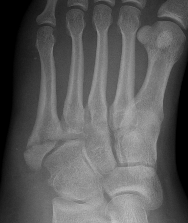

Base of 5th - Zone 1 / 2 / 3

Base Shaft Neck